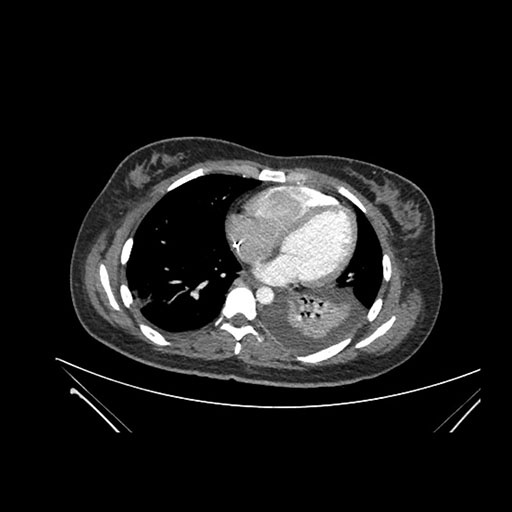

Imaging Analysis

Look through the patient's CT scan to identify any areas of concern for the necessary procedure.

Axial Venous